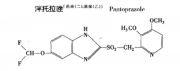

| 2021年7月26日 (一) 20:01 | 泮托拉唑结构.jpg (文件) |  |

19 KB | 77921020 | Uploaded with SimpleBatchUpload | 3 |